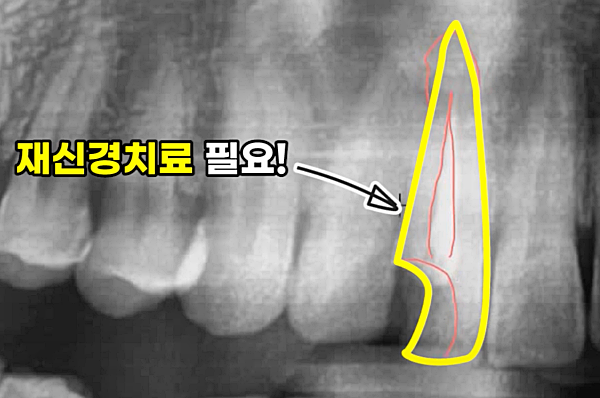

욱신욱신, 찌릿찌릿!! 분명 신경치료를 받고 왔는데 왜 치아 통증이 사라지지 않을까요? 고기를 좋아하는 음식물이 치아에 많이 끼는 편이에요. 그래서인지.... 최근 신경치료했던 부위의 치아와 잇몸에서 통증을 자주 느끼고 있었어요. 치과에 문의해 봤더니, 재신경치료가 필요할 수도 있다고 하셨어요. 이게 웬 날벼락! 신경치료가 얼마나 불편했는지 기억이 나면서 꼭 신경치료를 다시 해야 하는지 궁금하기 시작했습니다.

신경치료는 치아 내부의 감염된 신경을 제거하고 멸균 처리 후 밀봉하는 치료입니다. 하지만 다양한 이유로 처음 신경치료가 완벽하게 이루어지지 않을 수 있습니다. 마치 숨바꼭질처럼 치아 깊숙한 곳에 염증이 숨어있거나, 미세한 틈으로 세균이 다시 침투하는 경우가 발생하는 것이죠.

- 미세한 신경관까지 완벽히 신경이 제거되지 않은 경우: 복잡한 치아 신경관 구조 때문에 꼼꼼하게 제거하기 쉽지 않아 염증이 재발할 수 있습니다.

- 신경치료 후 시간이 지나면서 충전재에 미세한 틈이 있는 경우: 아무리 꼼꼼하게 밀봉해도 시간이 지나면서 충전재에 미세한 틈이 생길 수 있으며, 이 틈으로 세균이 침투하여 염증을 일으킬 수 있습니다.